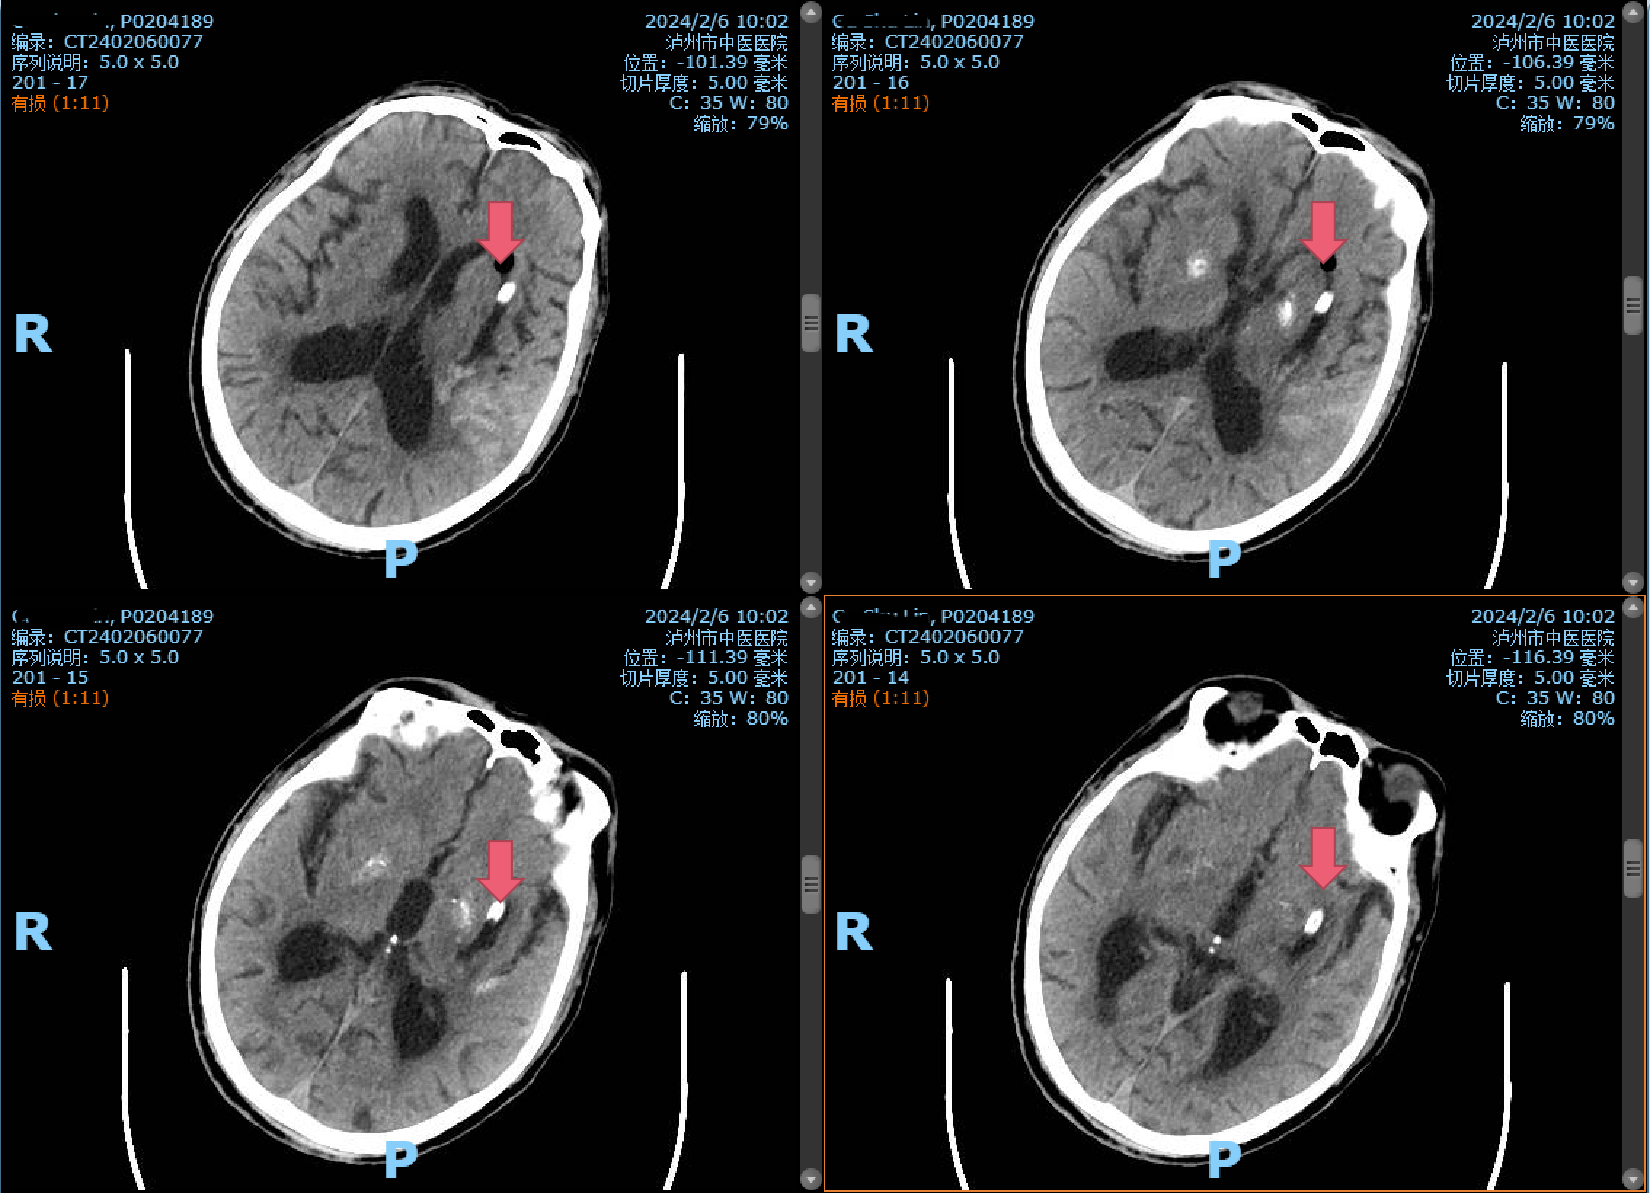

術(shù)前CT:左側(cè)基底節(jié)區(qū)腦出血伴血腫形成(紅色箭頭所指)

時(shí)間第一,生命至上。患者入院后直接經(jīng)急救通道,完善頭顱CT,提示腦出血,病情危重,立即及時(shí)、安全地送到了市中醫(yī)院重癥監(jiān)護(hù)室,并通知神經(jīng)外科。入院后由首診醫(yī)師曹飛副主任醫(yī)師接診。經(jīng)過仔細(xì)詢問病史、查體發(fā)現(xiàn)患者昏迷不醒,呼之不應(yīng)、無言語。雙瞳形圓不等大,向左凝視,左側(cè)瞳孔直徑約2.5mm,對光反射消失;右側(cè)瞳孔直徑約3mm,對光反射消失。右側(cè)肢體肌肉張力高,病理征陽性;結(jié)合CT片后診斷為:左側(cè)基底節(jié)區(qū)腦出血伴血腫形成。